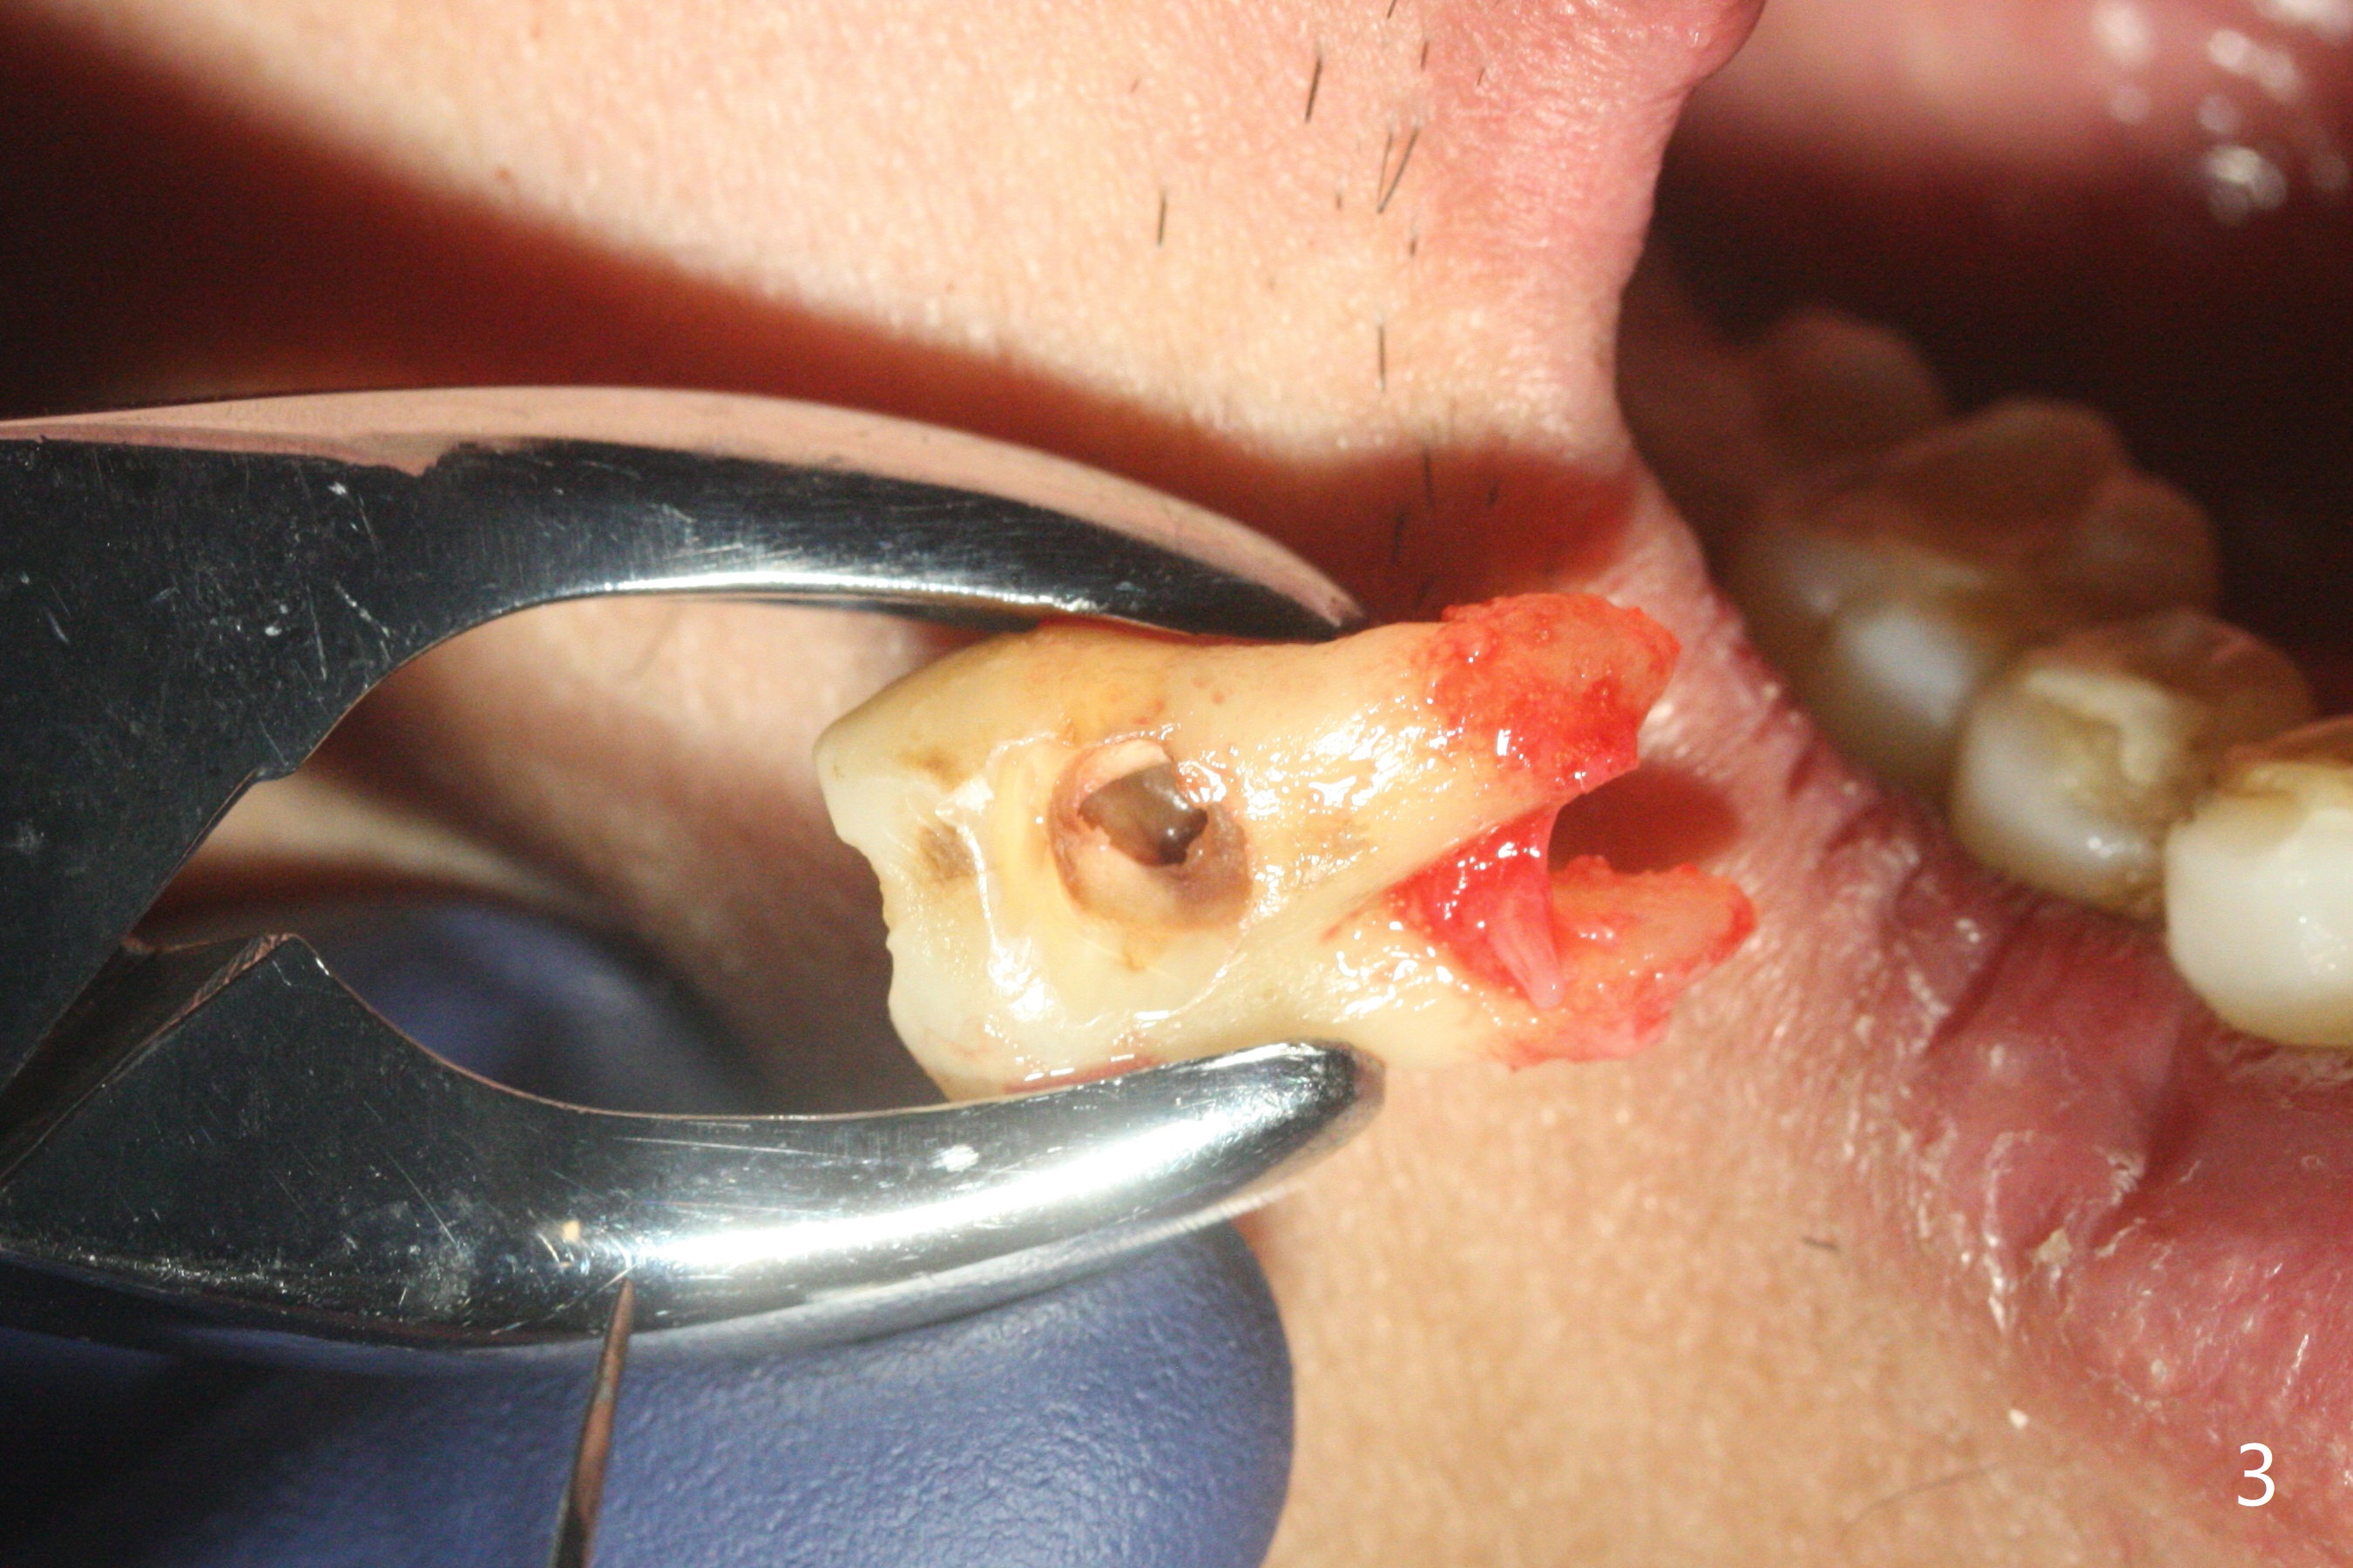

P3作为牙周膜刀

69岁,1号牙无症状(图一),去外州照顾孙子前,准备修补或者拔除,去龋后发现涉及牙髓(死髓),使用P3(图二)试图切断牙周膜,但是发觉不是很利索(图三),有什么窍门?